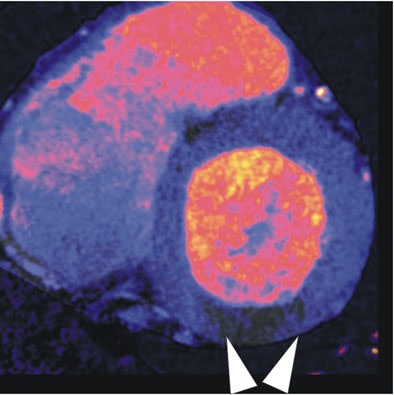

![]() |

| In a 64-year-old man with chest pain, image of the corresponding slice shows inferior ischemia (arrows). |